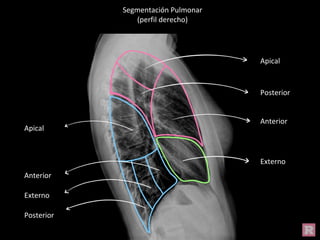

Segmentación Pulmonar

(perfil derecho)

Apical

Posterior

Anterior

Externo